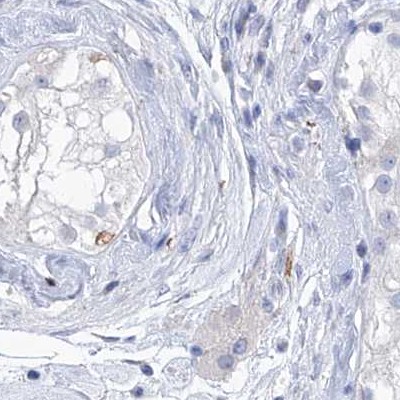

Immunohistochemical staining of human fallopian tube, kidney, lymph node and testis using Anti-C1orf87 antibody HPA031368 (A) shows similar protein distribution across tissues to independent antibody HPA031366 (B).